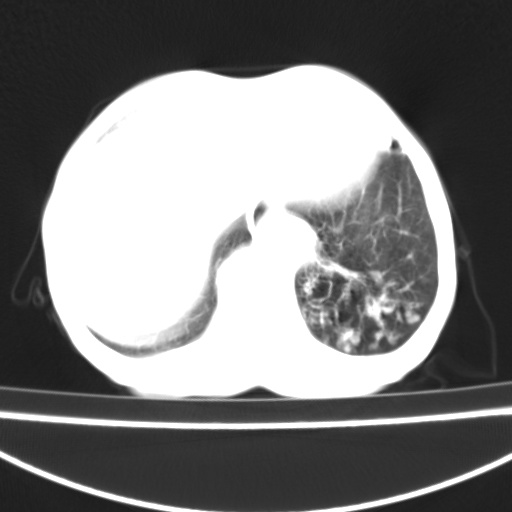

患者 女 67岁,反复咳嗽咳痰2年,加重伴喘及双下肢浮肿1月

诸大血管及f肺门血管增粗迂曲.左下肺多发薄壁空腔影.部分非也透亮度增高.薄曾扫描可区分肺气肿类型.考虑1.慢性支气管炎 2.左下肺支气管扩张 3.肺气肿 4 肺动脉高压5.是否有先心病病史

考虑1.慢性支气管炎 2.左下肺支气管扩张 3.肺气肿 4 肺动脉高压

慢支炎、肺气肿、双肺感染、左下囊状支扩。

慢支、肺气肿、肺动脉高压;左下肺囊状支扩并粘液栓形成。